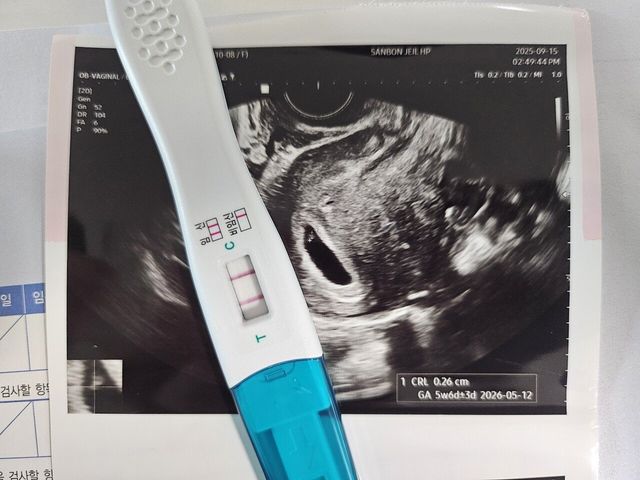

알고 봤더니 두 줄.. !!??

1755057941077.jpg 알고 봤더니 두 줄.. !!??

20250915_154331.jpg 알고 봤더니 두 줄.. !!??

근래에 일이 정신없을 정도로 너무 바빳는데

앞으론 더 열심히 살아야 할 이유가 생겼네요..

14개월 된 첫째데리고 병원가서

둘째 녀석 심장소리 듣고 왔습니다.

0.2mm라네요

와이프가 아파서 약먹기 전에 찝찝해본 임테기로

알게된 둘째인게 유머..ㅋㅋㅋㅋㅋㅋㅋ

둘 째.. 합법적 포빨이 가능할까요..?